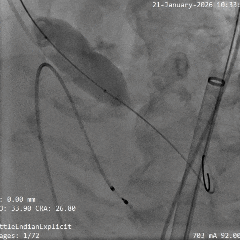

术中影像

根部造影

瓣叶钙化明显,瓣叶活动差,中度反流

直头导丝顺利跨瓣

猪尾导管测量跨瓣压差约60mmHg

20mm球囊预扩

小弯侧微腰,少量漏,左冠显影,右冠无显影

瓣膜0位初始定位释放

全展开位造影评估

瓣下约 3mm,左右冠均显影,少量反流

瓣膜稳定脱钩

无位移,无弹跳,无张力释放

根部造影评估

位置可,形态受限,可见中重度反流,左右冠均显影

20mm球囊后扩

可见瓣架底端扩开,瓣膜形态改善

最终造影可见瓣周漏,符合术前预判

超声可见左无对合缘轻度反流,整体瓣架形态较圆,左无钙化处呈“D”型,测量峰值流速为1.6m/s